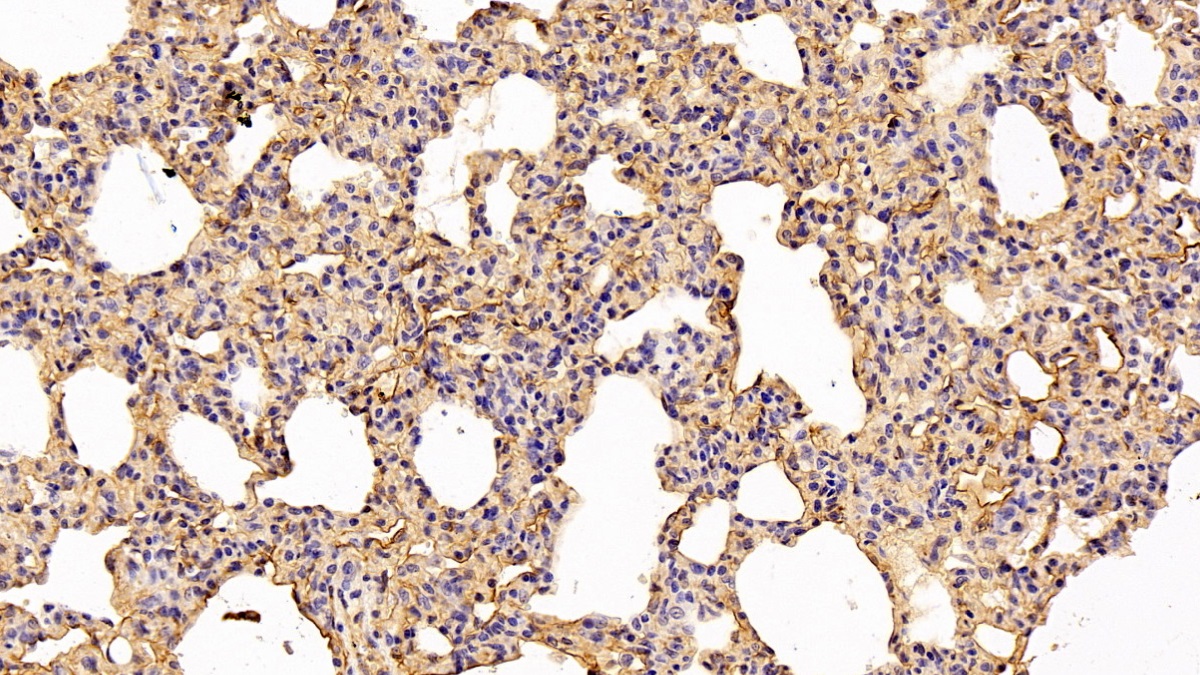

Использование высококачественных первичных антител является неотъемлемым условием получения точных и воспроизводимых результатов в современных научных исследованиях. Например, в рамках онкологического исследования удалось достоверно идентифицировать экспрессию белка PD-L1, что сыграло ключевую роль в оценке потенциальной эффективности иммунотерапии. Применение надежных антител обеспечило стабильность сигнала и высокую специфичность детекции, что позволило получить данные, пригодные для публикации в рецензируемых научных изданиях.